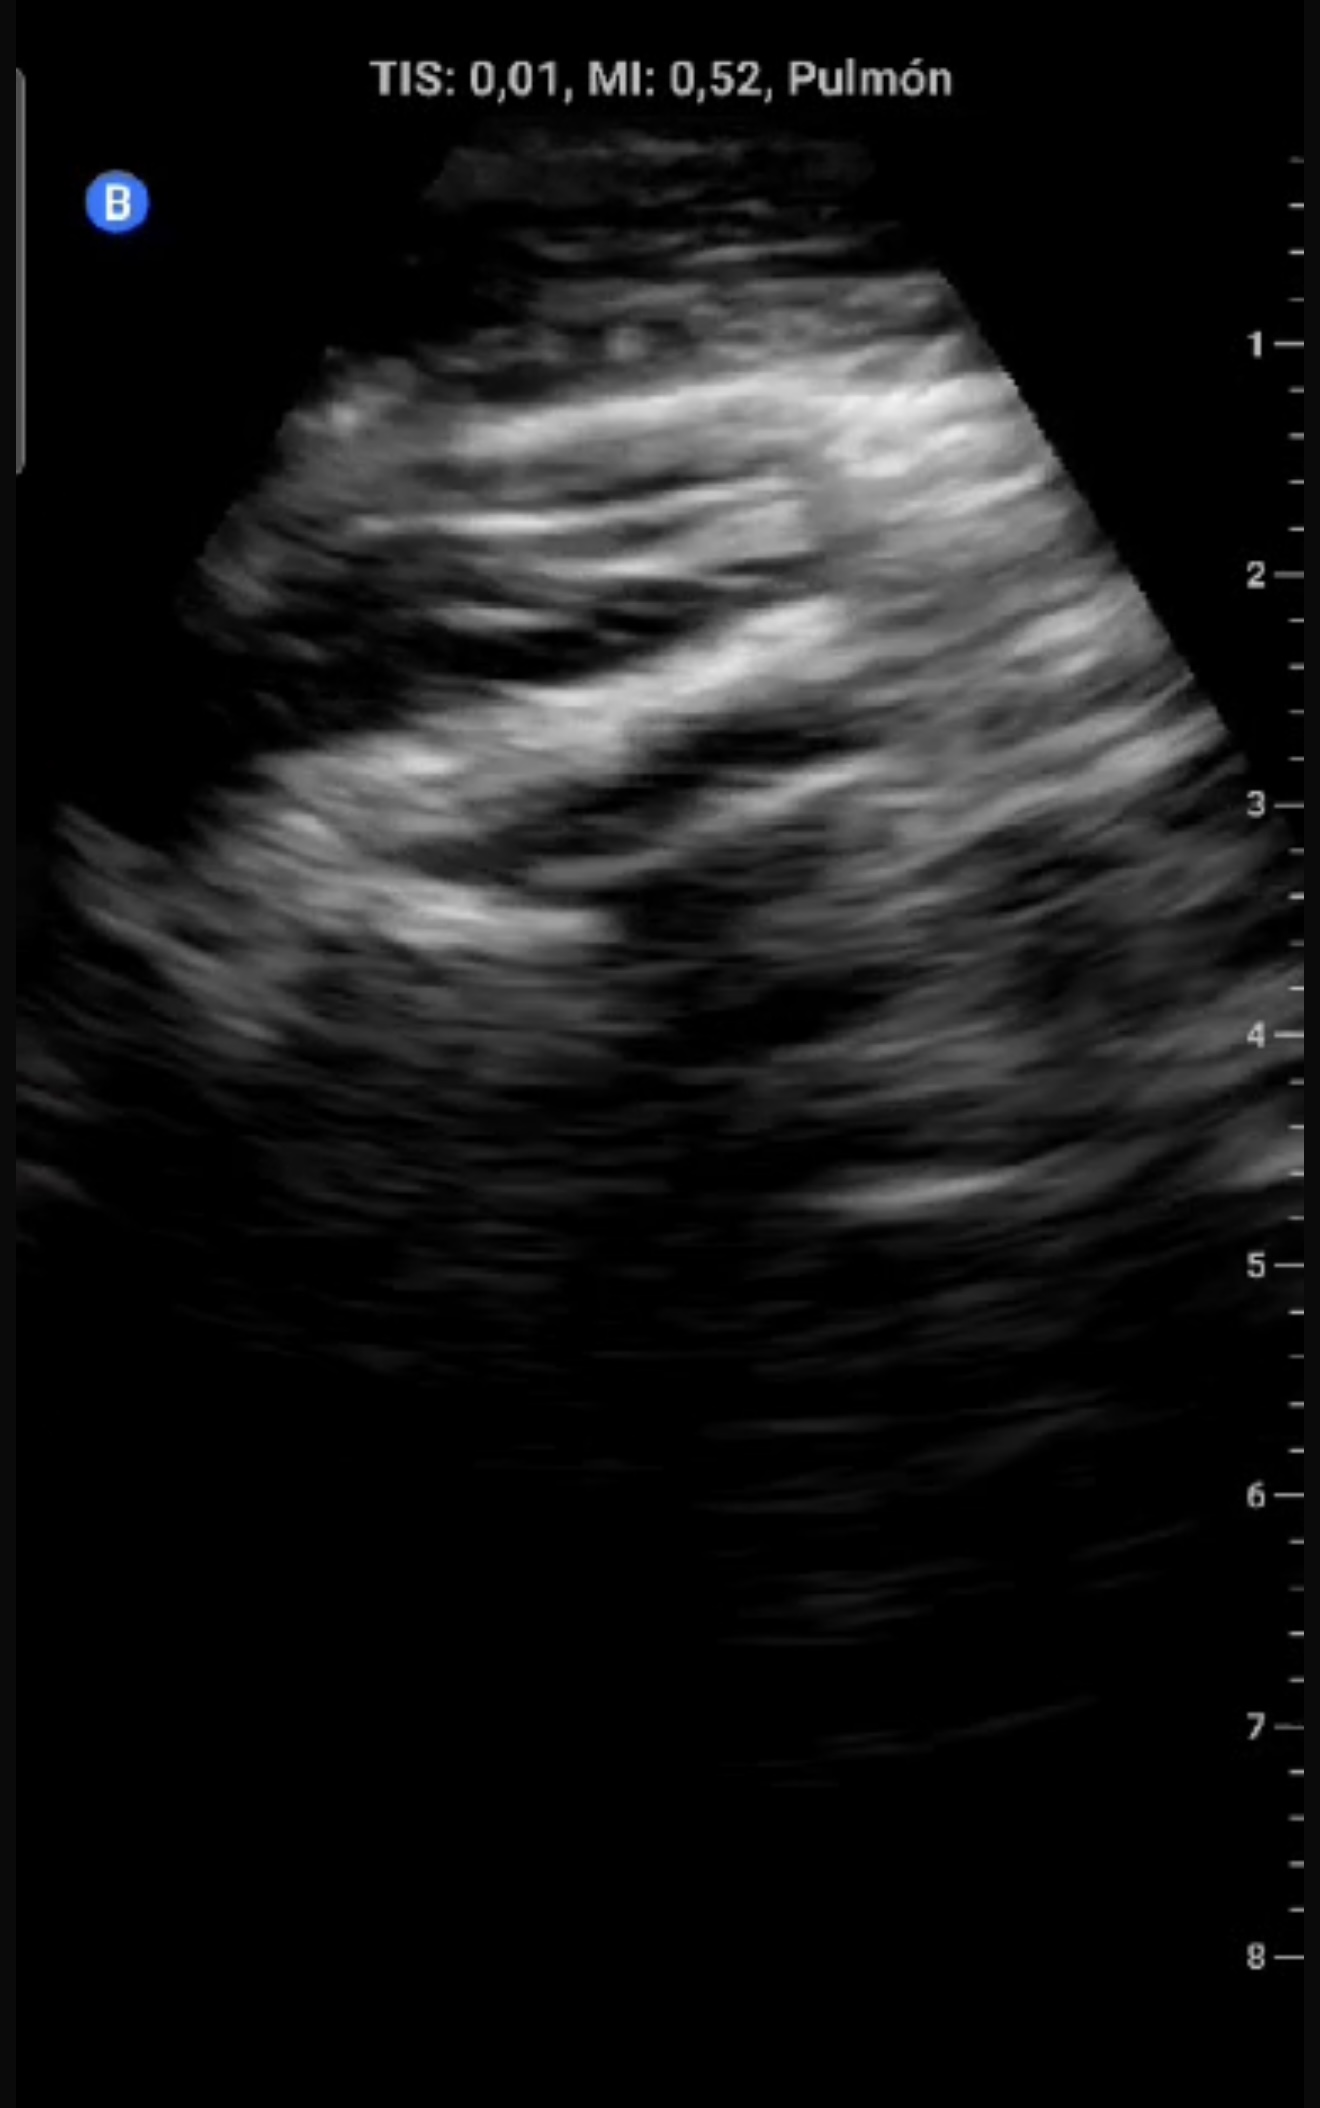

Eco clínica:

Ausencia de deslizamiento pleural (línea pleural fija), sugiriendo neumotórax.

Descripción de los hallazgos ecográficos

En modo B, ausencia de deslizamiento pleural con línea pleural estática hiperecoica. En modo M, signo de code bar (ausencia del signo de la playa).